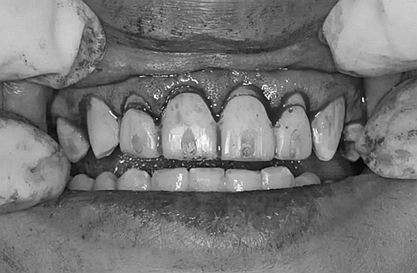

第5次復(fù)診的時候,終于讓我們4個兄弟恢復(fù)了正常的容顏。

現(xiàn)在剩下的任務(wù)就是為我其他的兄弟姐妹們治療了。需要做根管的做根管,需要做冠的做冠,需要樹脂充填的做樹脂充填。前前后后主人帶我們進行了12次的復(fù)診,歷時6個月,現(xiàn)在的我們是這樣的